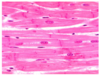

What type of ciliated epithelium is this?

What is the arrow pointing to?

What are the arrow heads pointing to?

Simple columnar

Smooth muscle

BALT